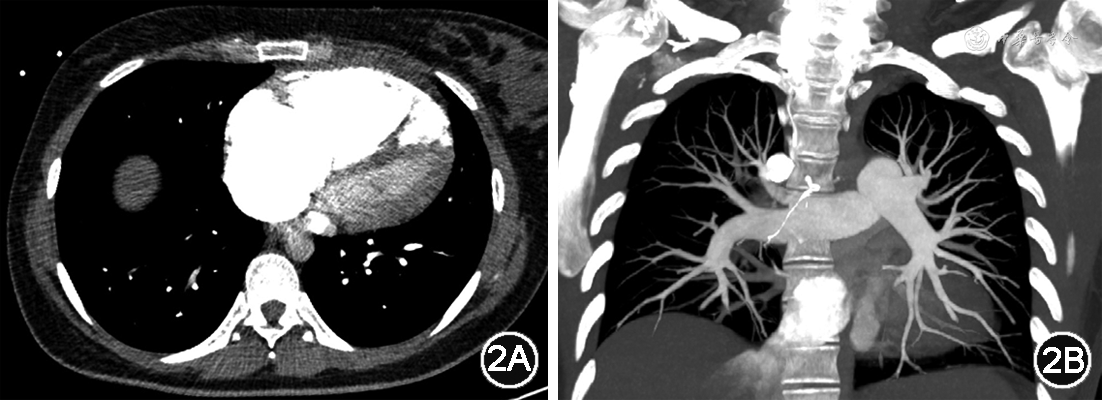

患者,女,28岁。因“妊娠30周零6日,活动时气短伴夜间平卧困难5日”于2023年3月18日来我院就诊。2022年11月30日患者因妊娠15周合并系统性红斑狼疮曾来我院产科就诊,产科超声提示胎儿无明显异常,由于系统性红斑狼疮未得到规范治疗建议终止妊娠,患者及家属拒绝,后未规律产检。2023年3月13日(妊娠30周零1日)时出现活动时气短,休息后可减轻,但不能完全缓解,气短进行性加重,3月17日时出现夜间平卧困难,伴心悸、背痛,遂于2023年3月18日就诊于我院急诊。既往确诊系统性红斑狼疮14年,累及皮肤和肾脏;2021年首次妊娠16周时发现高血压,产后血压恢复正常;否认糖尿病、冠心病等慢性病病史。入院体格检查:一般情况尚可,体温36.8 ℃,脉搏102次/min,呼吸20次/min,血压110/92 mmHg(1 mmHg=0.133 kPa),脉搏氧饱和度98%,颈静脉无怒张,四肢无水肿,双肺呼吸音清,未闻及干湿啰音,心率102次/min,律齐,P2>A2,未闻及明显杂音,腹部膨隆,可触及胎体,可闻及胎心。急诊入室立即行实验室检验:D-二聚体 1.16 g/L(0~0.55 g/L),高敏肌钙蛋白I 33 ng/L(≤34 ng/L),N末端B型利钠肽原(N-terminal pro-B-type natriuretic peptide,NT-proBNP)9 630 ng/L(0~125 ng/L);血气分析:pH 7.43(7.35~7.45),二氧化碳分压11 mmHg(35~45 mmHg),氧分压113 mmHg(83~108 mmHg),血氧饱和度98%(95%~99%),碳酸氢根浓度8.8 mmol/L(22.0~27.0 mmol/L),乳酸8.3 mmol/L(0.5~1.6 mmol/L);电解质正常;补体C3 0.474 g/L(0.730~1.460 g/L),补体C4 0.105 g/L(0.100~0.400 g/L),抗双链DNA抗体5.60 U/ml(阴性:<24.00 U/ml)。心电图提示:窦性心动过速,电轴右偏,V1导联R/s>1(图1)。床旁超声心动图提示:右心室前后径35 mm,左心室舒张末期内径32 mm,左心室射血分数66%,右心增大,右心室室壁活动降低,估测肺动脉收缩压76 mmHg,重度肺动脉高压。CT肺动脉造影提示:未见明显肺动脉栓塞征象,右心明显增大,左心受压,肺动脉高压、右心压力增高可能大(图2)。产科超声提示:单胎,胎头位于脐上,可见胎心搏动。